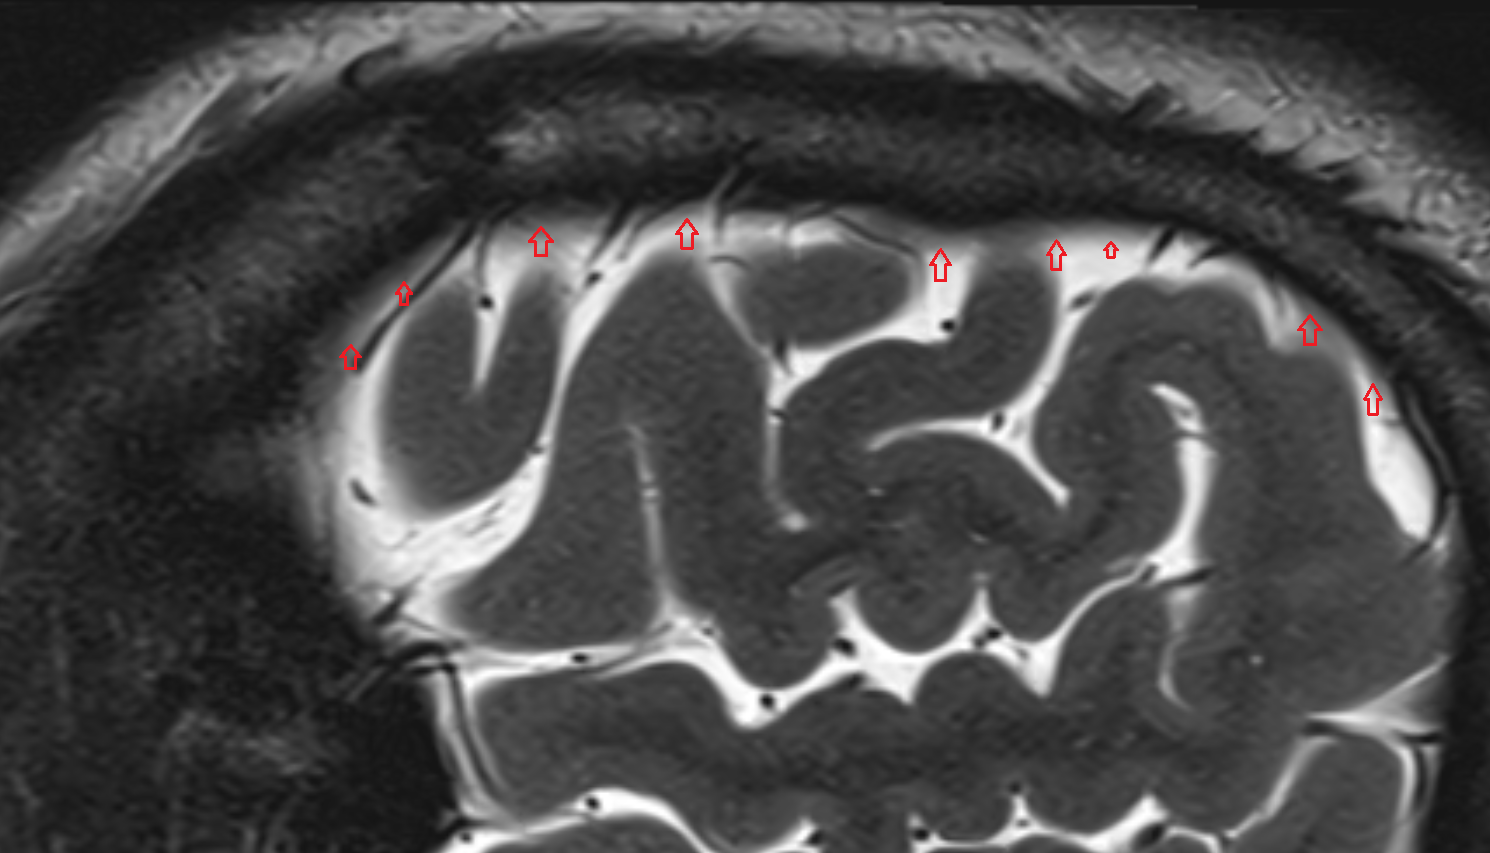

- Fetal brain

- Fetal cerebellum

- Fetal occipital lobe

- Fetal temporal lobe

- Fetal parietal lobe

- Fetal frontal lobe

- Fetal third ventricle

- Fetal fourth ventricle

- Fetal lateral ventricle